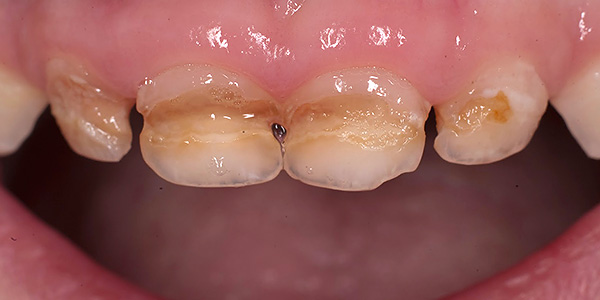

A foto abaixo mostra um exemplo de um dente da frente quebrado a ser removido:

A natureza da preparação depende dos recursos de manipulação futura (com ou sem anestesia, com ou sem sedação), mas as etapas mais básicas incluem: